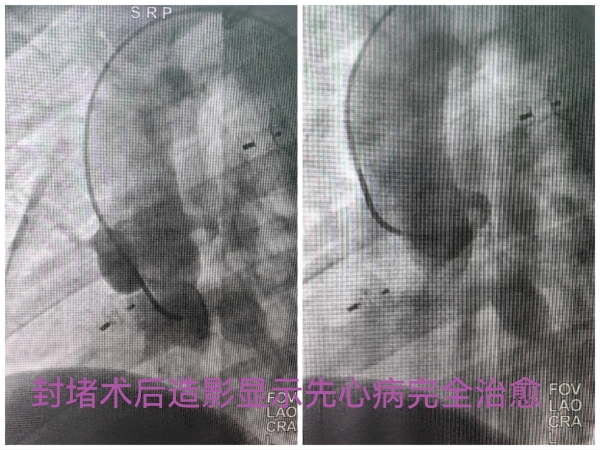

第一次经皮动脉导管未闭封堵手术完成很顺利,在抗凝临床药师季美汐的协助下,手术期间患者凝血功能控制良好,局麻下不到一小时的封堵手术出血仅10ml,术后第二天即出院。在一期手术后闫女士和孩子定期来院复诊,检查结果甚至比预期的更令人满意。中度肺动脉高压逆转下降为轻度,心脏形态较前缩小,三尖瓣反流也明显减少。良好的术后改变给了医患双方极大的信心,在一期术后半年患者再次入住心血管外科,按照计划再次手术矫正其余心脏畸形。考虑到二期术前心脏恢复情况超出预期,再次全面评估患者心脏病变后,相里伟医生提出改变原计划外科手术方式而先尝试用介入封堵治疗室间隔缺损的方案。尽管介入治疗有明显的微创优势,但根据术前影像学检查评估,室间隔缺损同三尖瓣关系密切,可能封堵会影响三尖瓣功能导致手术失败,仍然需要再次外科手术,会增加医疗费用和损伤风险。令人欣慰的是,当谈及介入手术的顾虑时,患者和家属毫不迟疑的选择了信任。如同术前所预料,二期手术中遇到技术和耐心的极大挑战,心室内的假腱索导致输送轨道建立困难,右心室对于刺激极其敏感,室性心律发作频繁多次不得不暂时中断操作,周边组织结构复杂导致封堵器大小的艰难选择等,当诸多障碍被一一克服,当封堵器完全释放后,术中超声证实室间隔水平异常分流完全消失,临近瓣膜的功能不受影响,心脏搏动保持正常节律,介入封堵手术获得成功,身着数十斤铅衣的相里伟和张忆雯两位医生的努力得到了最好的结果。当好消息在第一时间传到手术室外焦急等待的家属时,闫女士难以抑制自己复杂的心情,热泪盈眶无语成咽。术后的事情简单有序,第二天正常恢复日常活动,复查各项检查和凝血指标都正常,三天留院观察后,历时六个月的两次心脏手术治疗达到了安全、极简和经济的完美结局。